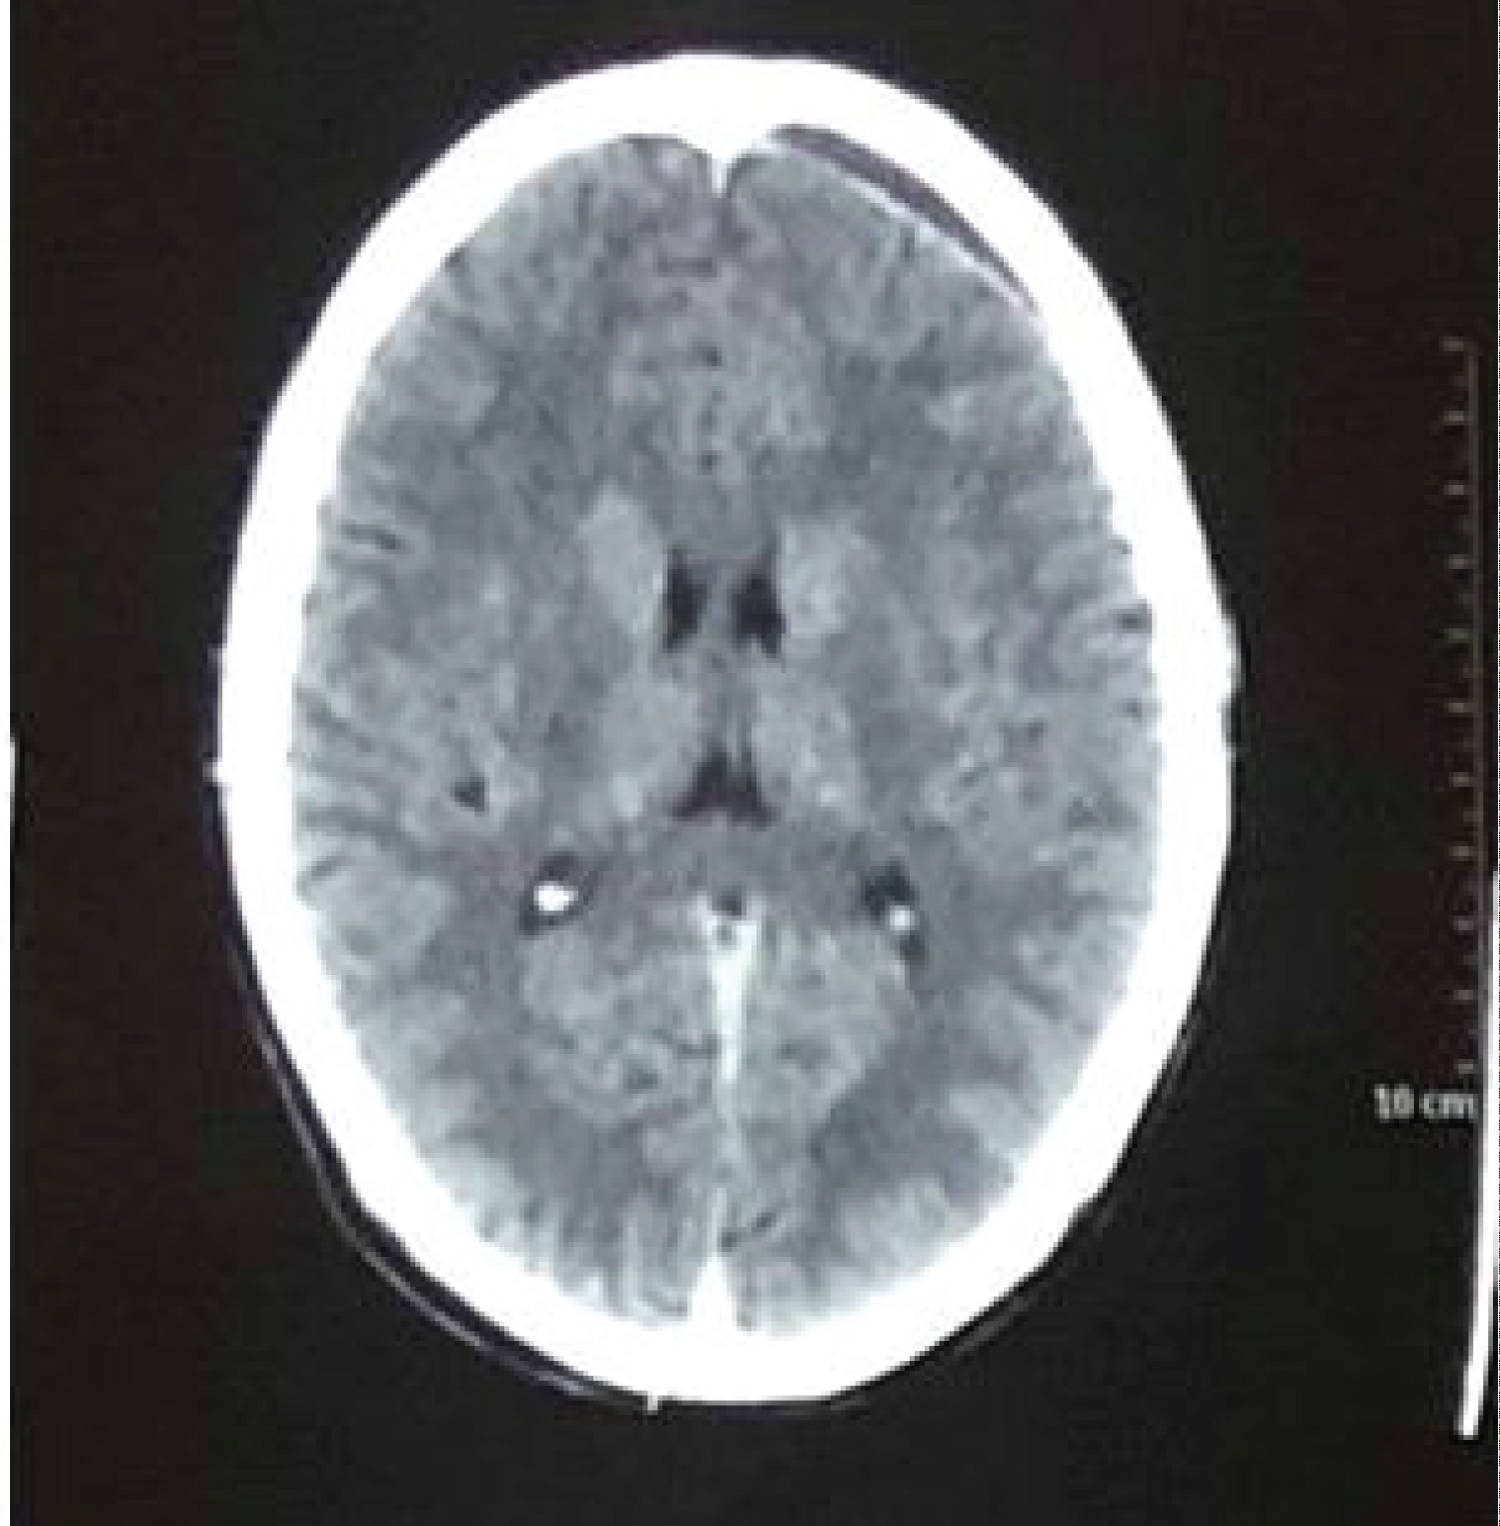

He was reluctant for opting any surgical intervention. Patient was advised to report urgently to hospital if develops any symptoms suggestive of raised intracranial pressure e.g., seizures, repeated vomiting, weakness of any limb, drowsiness, or unconsciousness. Patient was kept on symptomatic treatment in the form of analgesics and regular neurological assessment. Gradually his headache even regressed completely within a week. EDH was regressing in repeat CT scan head which were done thereafter, and CT scan head done after twelve weeks showed near complete resolution of left fronto parietal EDH (Figure 3).

Figure 3: CT scan head (after 12 weeks), showing near complete resolution of left frontoparietal extradural haematoma. View Figure 3